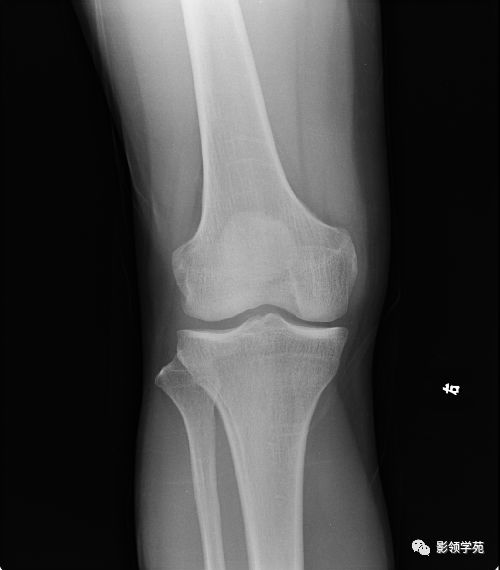

因此,從定義上來看,骨挫傷并不是骨折。其中,碾挫傷也被稱為離斷傷,分為不完全離斷和完全離斷兩種。然而,骨挫傷對工傷家屬來說可能會造成很大的痛苦。因為骨挫傷通常會伴隨著關節韌帶軟組織損傷等,最常...